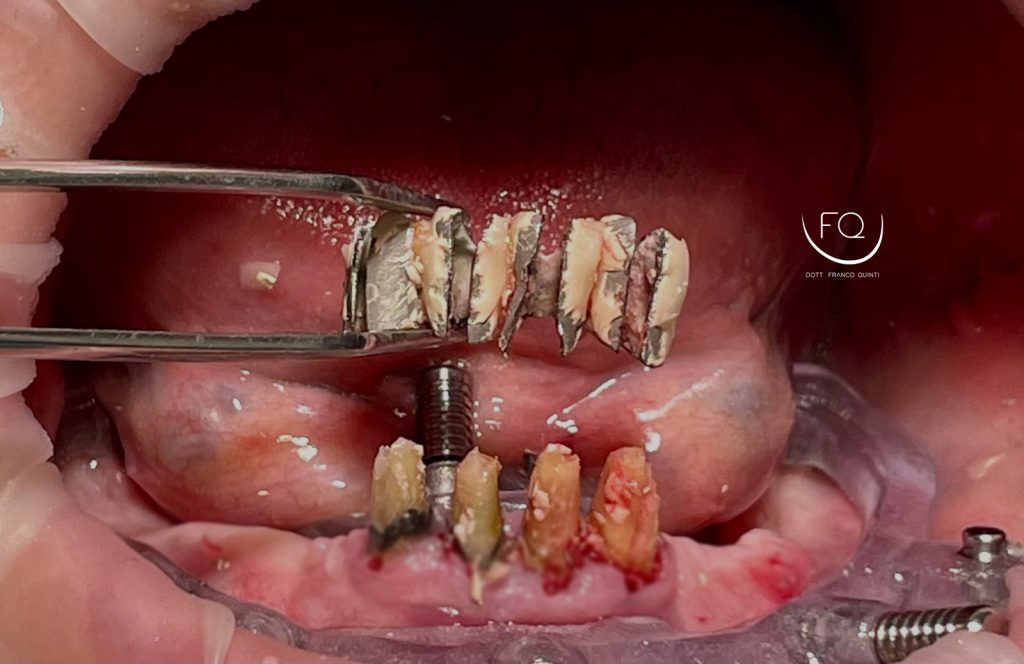

Oggi vi presento un caso di riabilitazione dell’arcata inferiore eseguito con l’utilizzo di dime scomponibili.

Il trattamento ha previsto l’inserimento di 4 impianti Prama Power di Sweden & Martina e la contestuale riabilitazione protesica provvisoria. Tra 3 mesi il caso verrà finalizzato con una protesi definitiva.